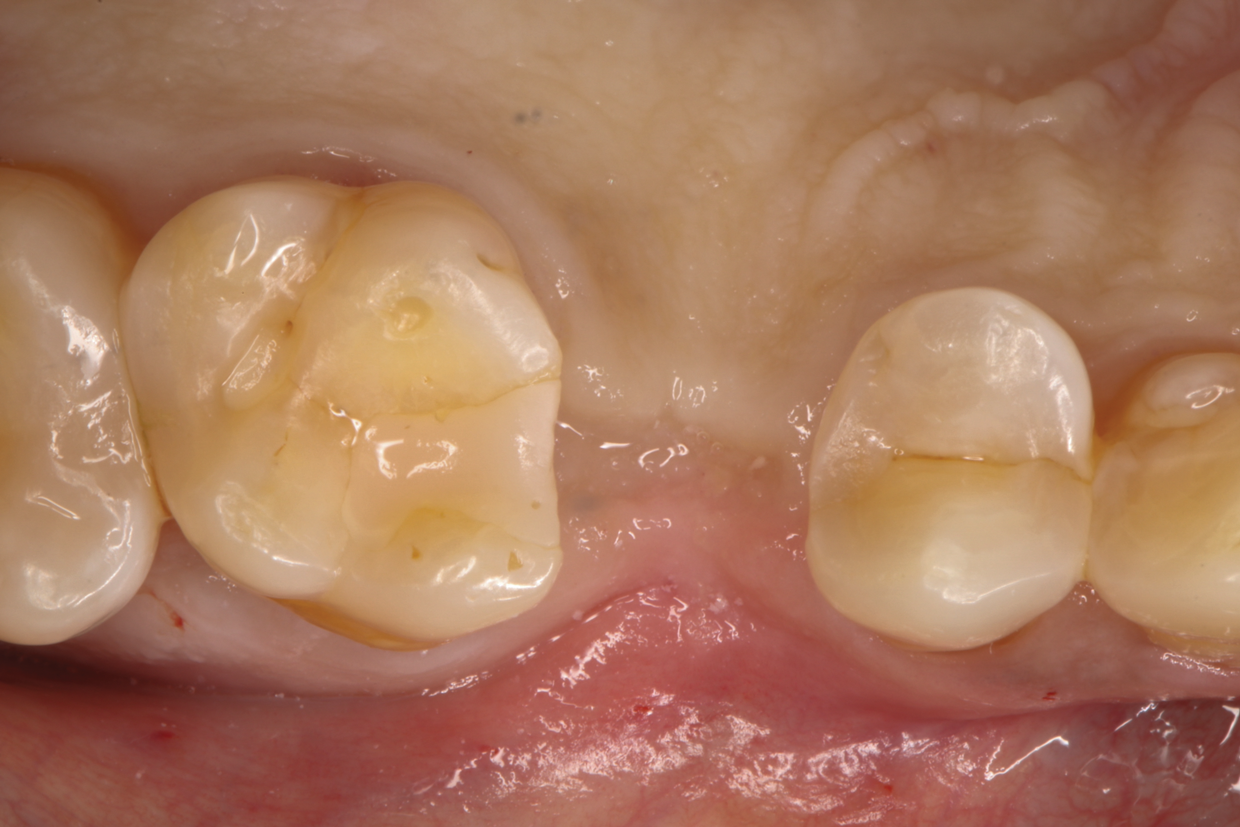

The patient returned 4 months later for implant placement with complete wound healing observed (Figure 7). Following local anesthesia via infiltration of 2% xylocaine with 1:100,000 epinephrine, a crestal incision was carried out over the edentulous area to allow for full-thickness flap elevation (Figure 8). Adequate alveolar bone dimensions for implant placement were observed (Figure 9). Optimal bone density and quality was confirmed during implant osteotomy preparation for placement of a 4.2 mm x 11 mm implant. Optimal insertion torque was recorded (45 Ncm). A healing cap was connected, and flaps were sutured with 4-0 absorbable sutures (Figure 10).

Fig 10. A healing cap was connected, and flaps were sutured with 4-0 absorbable sutures.

Figure 10